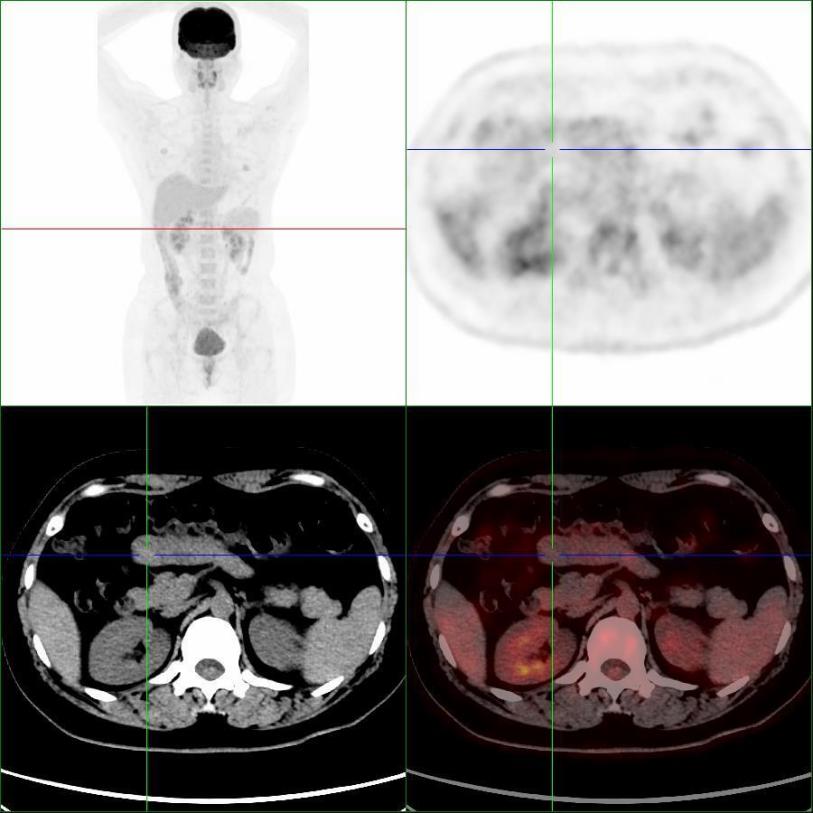

患者完善PET/CT檢查,小腸結(jié)節(jié)未見明顯代謝異常,考慮良性病變(圖2)。

圖2,PET/CT示小腸結(jié)節(jié)(十字線交叉處),呈低代謝表現(xiàn)

患者因有“惡性黑色素瘤”病史,對良性病變的診斷存在疑慮,遂進(jìn)行了小腸結(jié)節(jié)的手術(shù),行腹腔鏡探查+小腸腫瘤切除術(shù),術(shù)后病理考慮“異位胰腺”。

本例患者有"右胸壁惡性黑色素瘤"手術(shù)病史,且增強(qiáng)CT懷疑“神經(jīng)內(nèi)分泌腫瘤”,行PET/CT檢查目的是為了進(jìn)一步明確分期,指導(dǎo)后續(xù)治療。PET/CT表現(xiàn)為低代謝,提示良性病變,最終得到病理證實。PET/CT是分子影像學(xué)利器,能夠從代謝的角度提供信息,反映細(xì)胞活躍程度,為診斷帶來新的思路。惡性腫瘤或炎癥病變細(xì)胞葡萄糖酵解能力往往高于正常組織細(xì)胞,會大量積聚18F-FDG,從而被PET敏感地捕捉到。當(dāng)PET顯像為“陰性”顯像時,說明細(xì)胞代謝不活躍,更傾向良性病變。